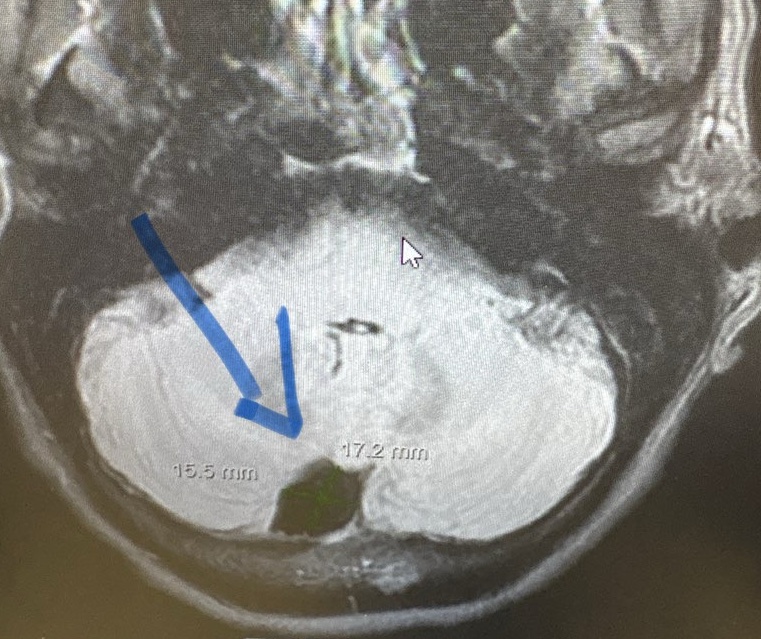

Our response and recovery followed the seasons. Fall was all about letting go, winter felt brutal and barren. Then came spring. For the first time we felt hope. For the first time we felt like we could look up. Life was starting to return to normal. Then a routine doctor’s appointment led to an ENT visit led to a head MRI led to the discovery of an acorn sized mass inside my skull.

A cyst. An “arachnoid” cyst. Benign. Maybe it’s been there a long time – like a really long time. Maybe even since birth. But then why have I been experiencing symptoms for the past four years? Are they even connected? And, when I feel pressure in my head, or pulsing behind my eye, or fullness in my ear, is it a harbinger of something worse happening? I didn’t know there was a difference between a neurologist and a neurosurgeon but I soon had visits with both.

Ultimately it was a neurointerventional radiologist who performed the cerebral angiogram this summer then sent me home with peace of mind that the piece of mind with a cyst did not pose any immediate or long-term risk and that I should manage symptoms and go about my life.